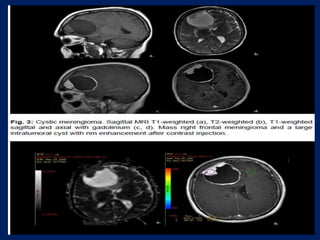

Intraventricular meningioma